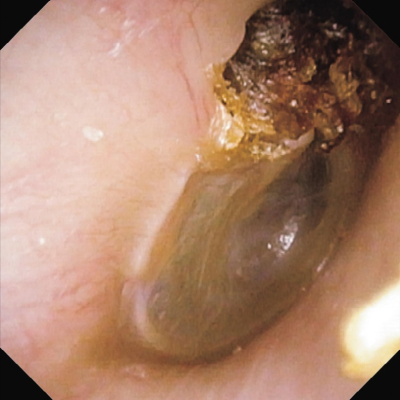

既往歴と家族歴とに特記すべきことはない。血液所見に異常を認めない。神経学的所見に異常を認めない。右鼓膜の写真と右側頭骨CTとを別に示す。